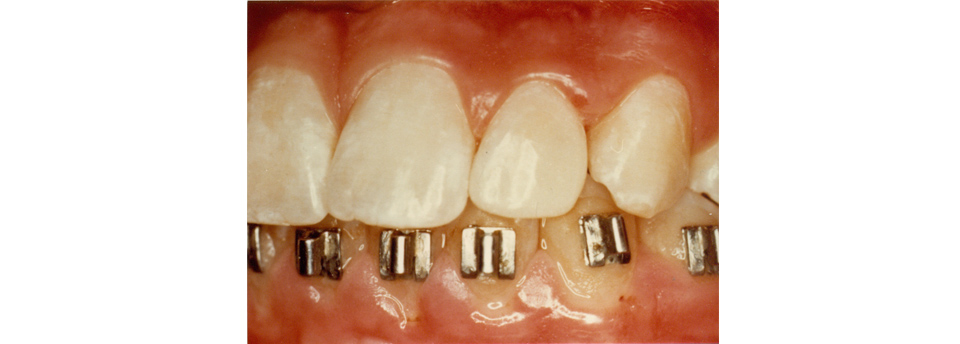

We enjoy working with children of all ages and feel it is very important to begin dental health early. Our patients are 3 years and up. Many dental problems can be intercepted and treated easily if diagnosed early. Our office offers sealants, fillings, crowns, extractions on “baby” teeth and adult teeth. We offer screening for future orthodontic treatment and have a wonderful team of specialists to help make difficult cases easy. Click here to find out more.